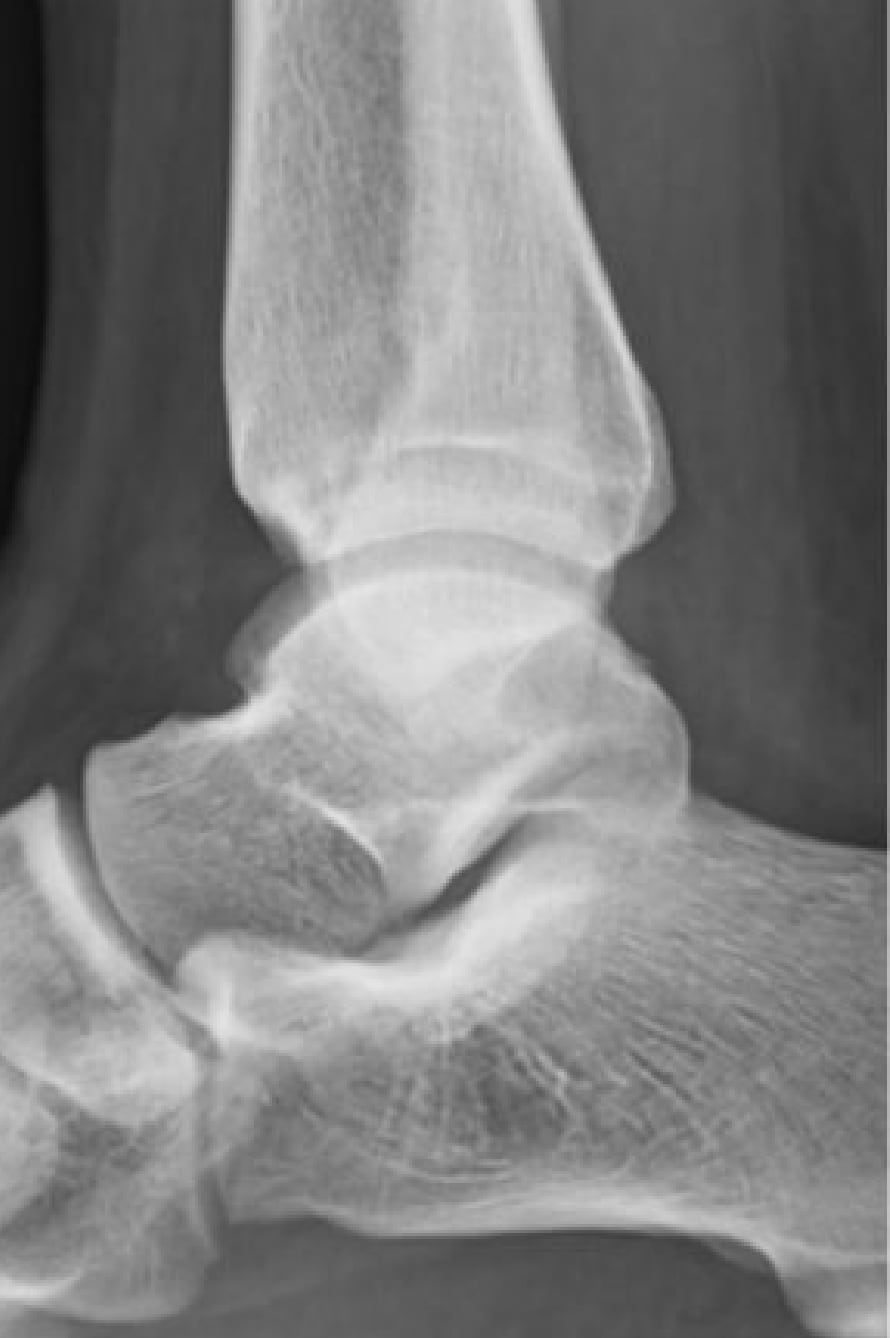

2020-12-09 スポーツ整形 ページ内リンク 後方インピンジメント症候群(三角骨障害)【スポーツ整形外科】 後方インピンジメント症候群(三角骨障害)【スポーツ整形外科】 サッカーやラグビーのキック動作やクラシックバレエのポアント肢位で足関節後方の骨が衝突して疼痛が発生する。⇒鏡視下切除により症状消失。 術前 術後 関連ページ スポーツ整形 一覧へ戻る